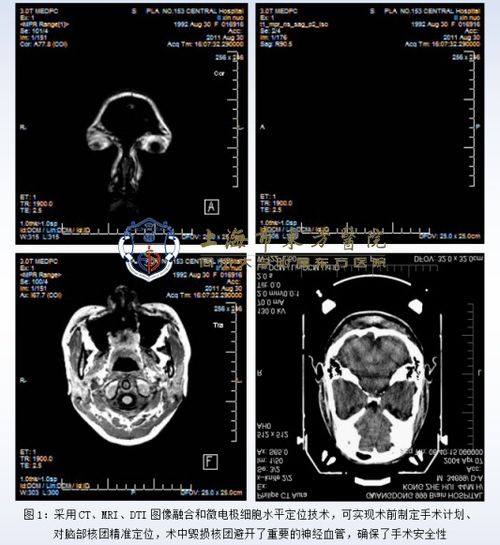

手术规划:CT扫描可以提供详细的内部结构信息,帮助医生进行手术规划。